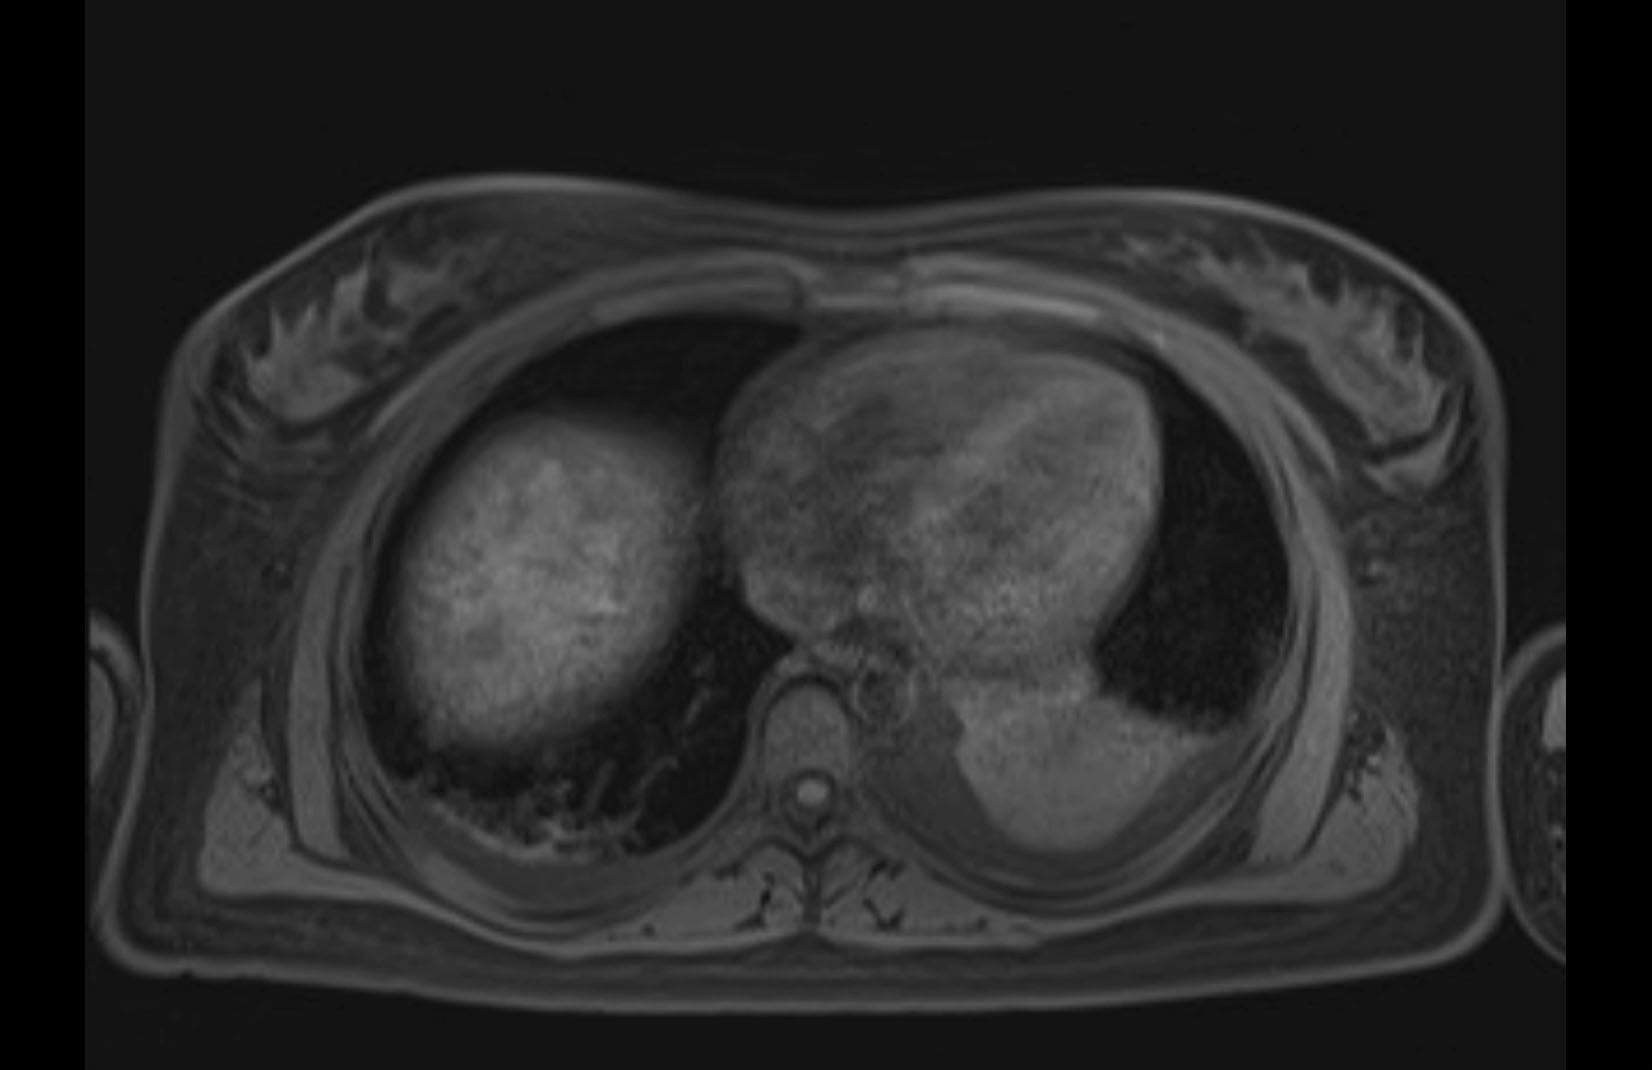

Imaging Analysis

Look through the patient's CT scan to identify any areas of concern for the necessary procedure.

MRI T2

Based on initial findings, which issue(s) would you be most concerned about?